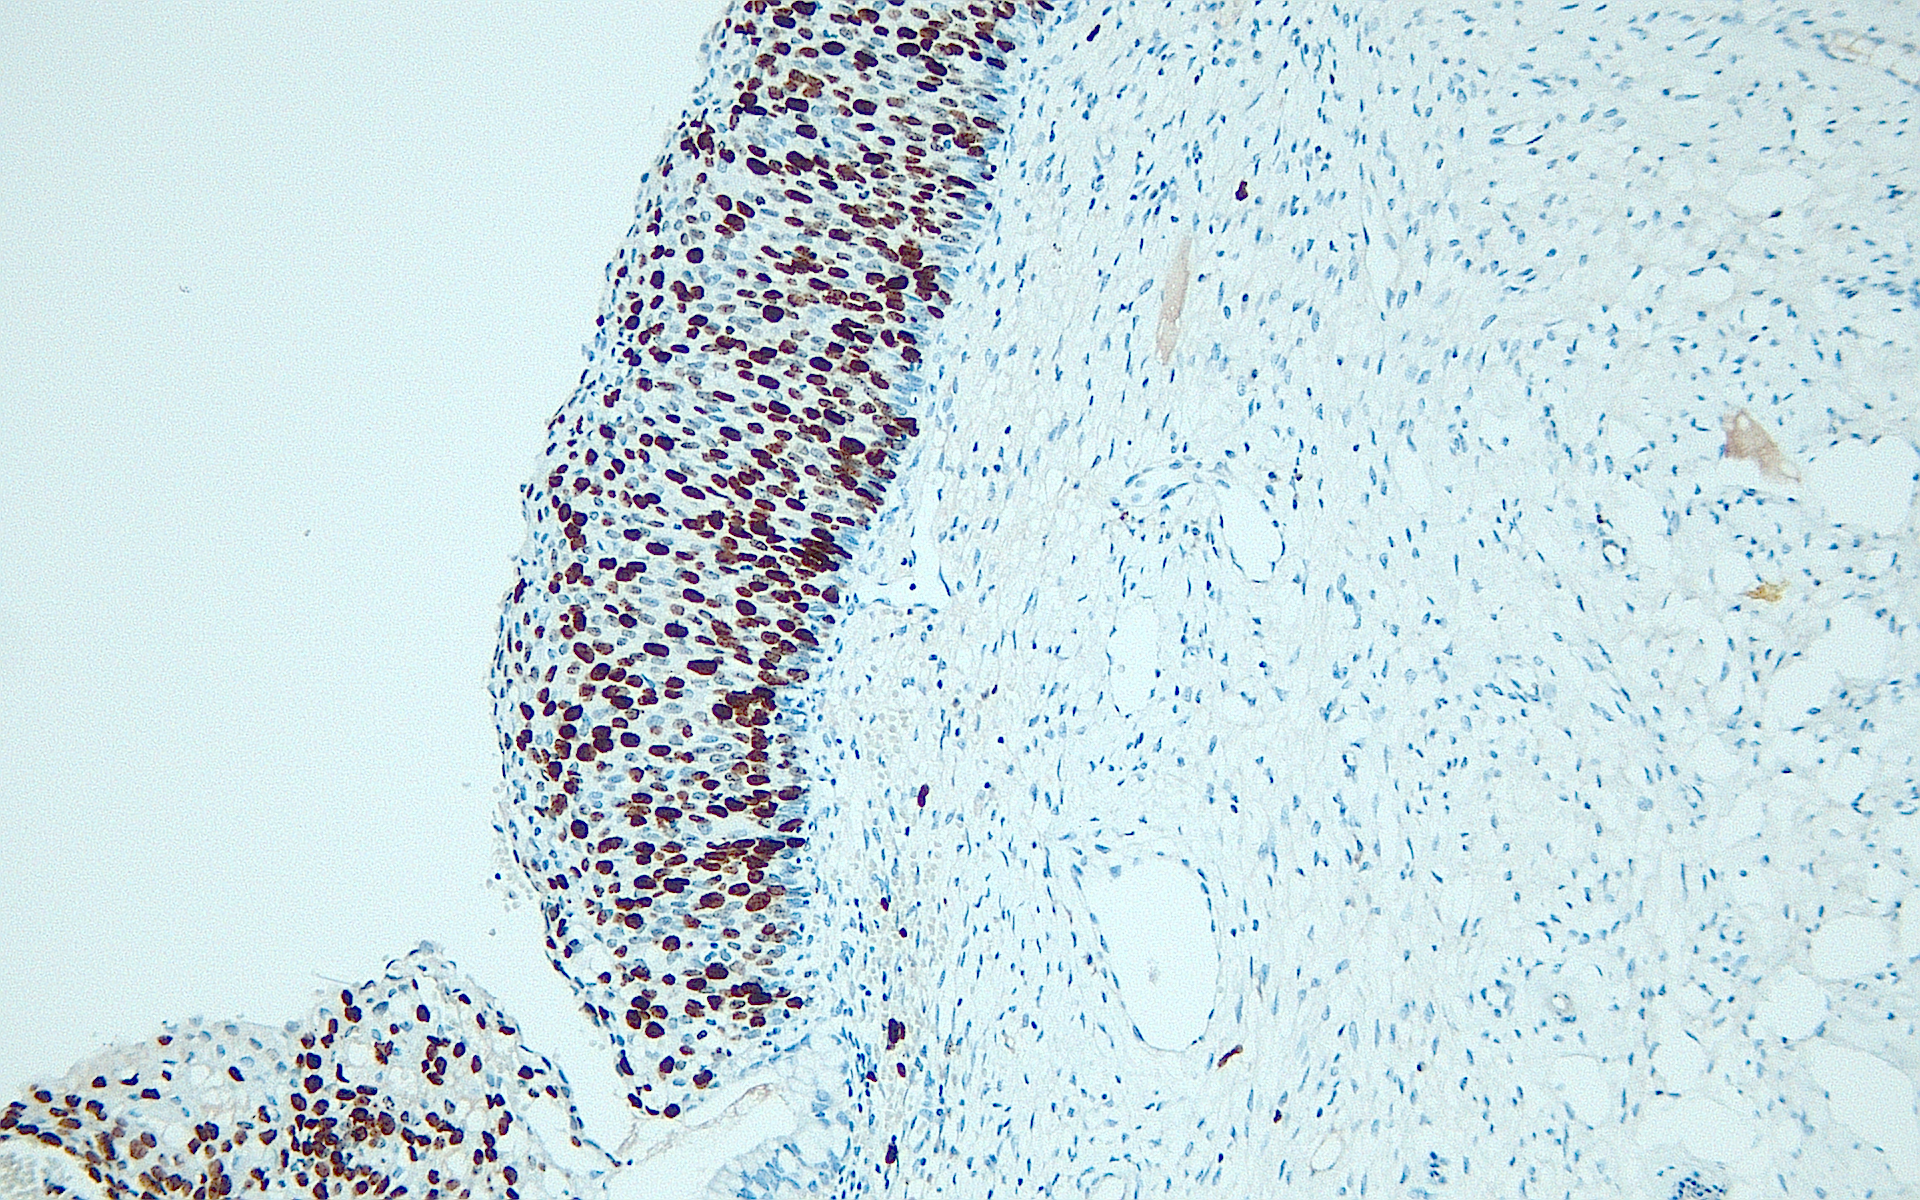

Anti-Ki-67

Product ID:DB 317 Category:IHC-P

IHC-P, dilution 1:100

DB-317-Ventana-png DB-317-Leica-png